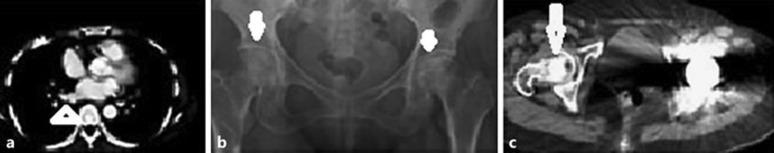

We report 2 cases of patients with solid tumors and coagulopathy who experienced avascular necrosis (AVN) of the bone following chemotherapy. Both cases exhibited nontraumatic bilateral AVN of the femoral heads, and one also showed bilateral AVN of the humeral heads. One case had multiple thromboembolic complications, including pulmonary obstructive syndrome and paraneoplastic pain. The other showed multiple paraneoplastic syndromes, with hypercalcemia and thrombocytosis. Groin pain and claudication of the lower extremities developed and persisted. Both patients eventually received bilateral hip arthroplasty due to AVN of both femoral heads.